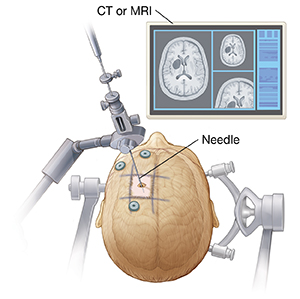

Stereotactic biopsy

This type of biopsy is often done if a tumor is not near the surface of the skull. A special frame may be put around your head to hold it still. A tiny hole is drilled into your skull and a long, thin hollow needle is put into your brain. The healthcare provider uses a CT scan or MRI images and a computer system to guide the needle into the tumor. A sample is then taken out through the needle.

During the biopsy, a small hole will be drilled in the skull. The surgeon will pass a hollow needle through the hole, into the brain and the tumor. Cells taken from the tumor will then be sent to a pathology lab to be examined.